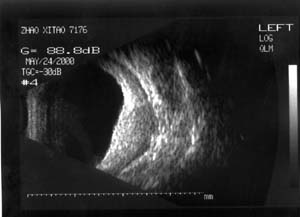

图1 患者男性,32岁。99年8月发现左眼球突出,当时按眶内炎症治疗无效99年12月左眼开始充血,反复发作(后来仅间隔1-2天),头痛。曾按“结膜炎、眼眶炎症”等治疗无效。2000年4月经CT检查发现左眼球外侧肿物,诊断:眼内肿物、眶内炎性假瘤?随来我院。入院检查:视力(戴镜)右眼1.0,左眼0.3,不能矫正。左眼睑肿胀,结膜混合充血,结膜下血管怒张(图1)。角膜正常,屈光间质清楚。眼底为高度近视眼底表现(-10D),眼球壁内下方6:00-9:00自视盘下方开始隆起(约+6D)。眼球突出4mm。B超及标准化A超显示左眼球内下方及下方巩膜肥厚,最厚处达7mm,可见明显筋膜囊水肿(图2)。CT显示左眼球内下方巩膜增厚,并向眼内隆起,筋膜囊水肿(图3)。

图2 B超显示眼球壁明显增厚